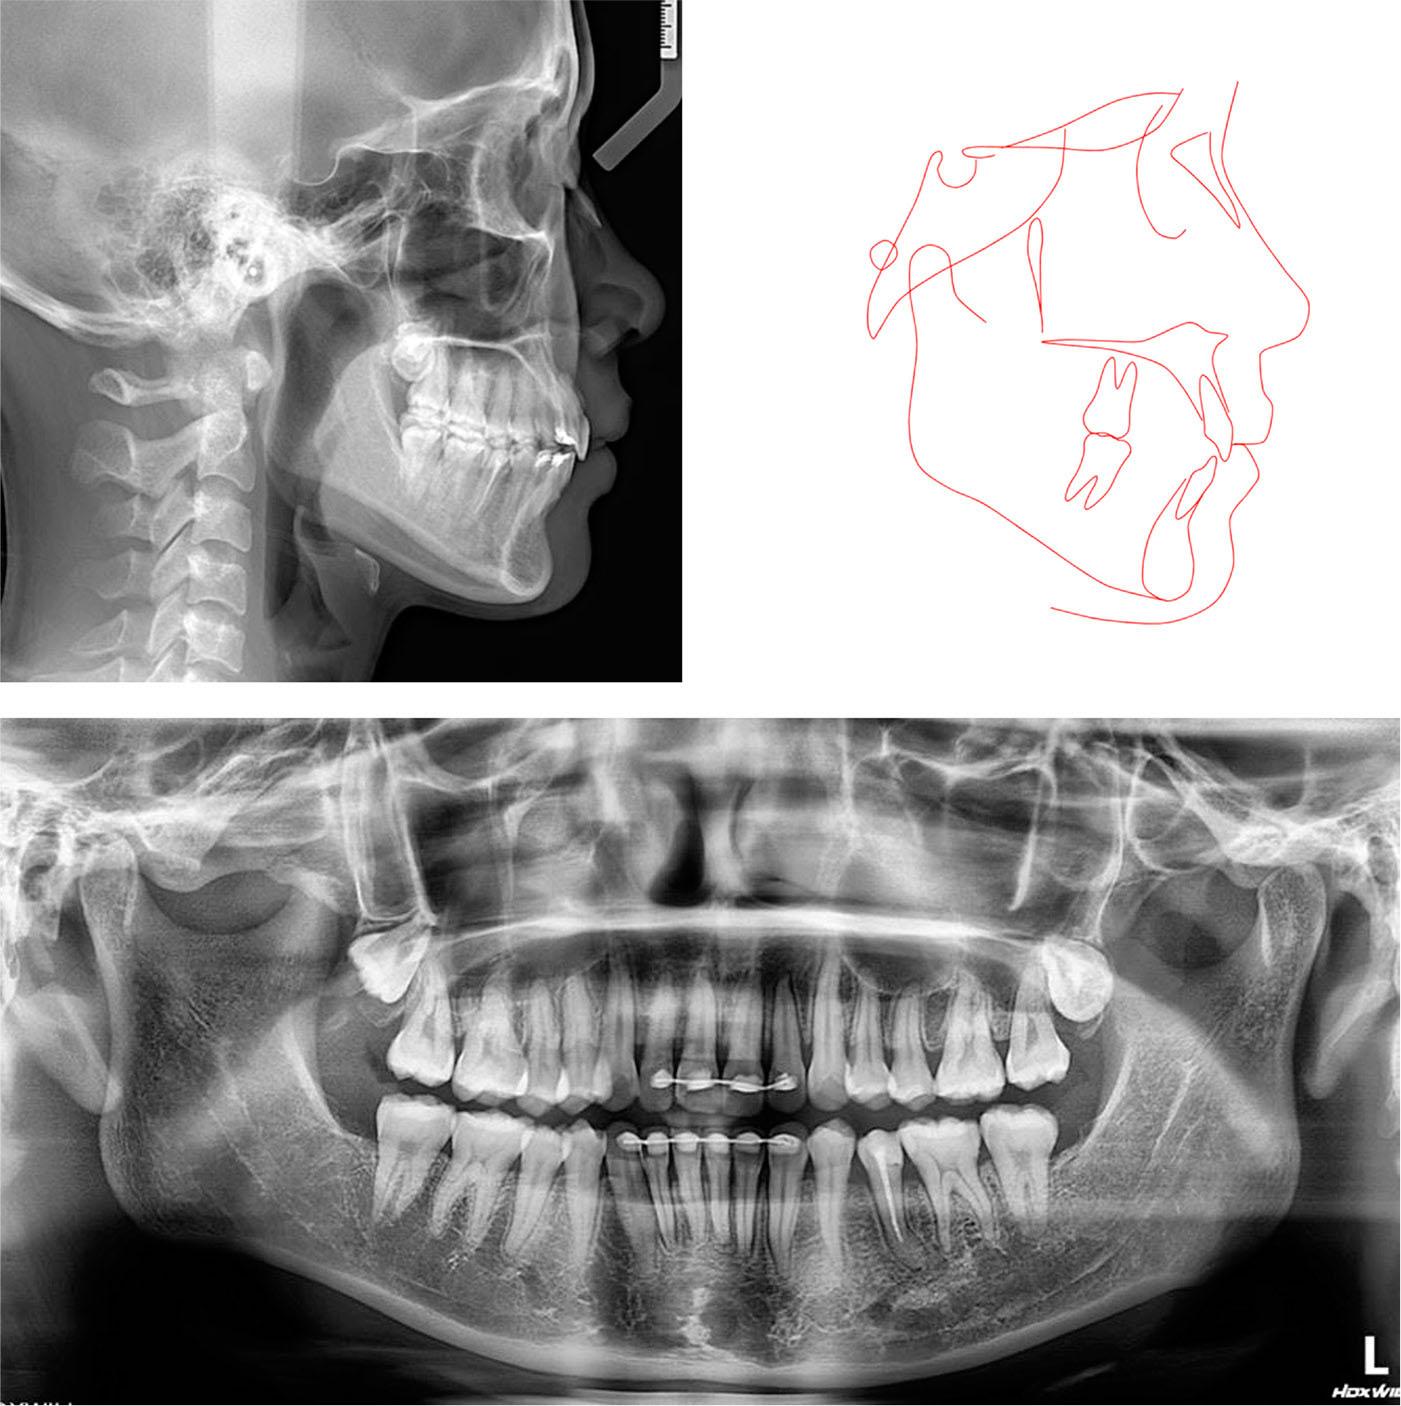

A lateral cephalometric analysis showed a reduction in the proclination of the upper and lower incisors (U1-SN, 96.7°; L1-MP, 94.1°) despite the non-extraction treatment strategy (Figure 11). The lower anterior facial height slightly increased (FMA, 27.8°). The upper and lower lip projections were maintained (upper lip to E-line, -1.4 mm; lower lip to E-line, -0.2 mm). The panoramic radiograph showed good root parallelism without signs of root resorption. The uprighting of the mandibular molars and second premolars was apparent. The cephalometric superimpositions further confirmed the retraction of the upper and lower incisors, the slight extrusion of the upper incisors, the intrusion of the lower incisors, and the uprighting of the mandibular molars (Figure 12).

Post-treatment radiographs and tracing.

Overall and regional cephalometric superimpositions of the initial (black) and final (red) lateral cephalometric tracings.